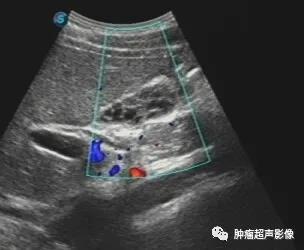

典型病例:蜂巢样胆囊的超声图像

蜂巢样胆囊:胆囊内见多处的细薄分隔,将胆囊全部或局部分隔为大小不等的囊腔结构,断面上类似于蜂巢,故得名。

超声表现:胆囊整体或局部表现为大小不等的囊腔结构,这些囊腔相互联通,囊腔之间为细薄的高回声分隔,呈蜂巢样。

男,31岁体检发现,胆囊类似蜂巢(病例来自微信会诊)